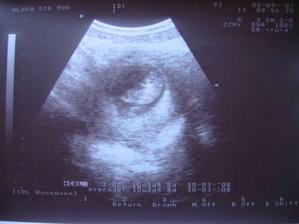

Terezka přiletí v dubnu

Týden po svatbě jsme zjistili že už měsíc pod srdíčkem mi roste nový život,byl to nejkrásnější den v životě.Ve 20.týdnu jsme byli na velkém ultrazvuku a tam nám doktor řekl, že čekáme zdravou holčičku, na kterou se moc těšíme.